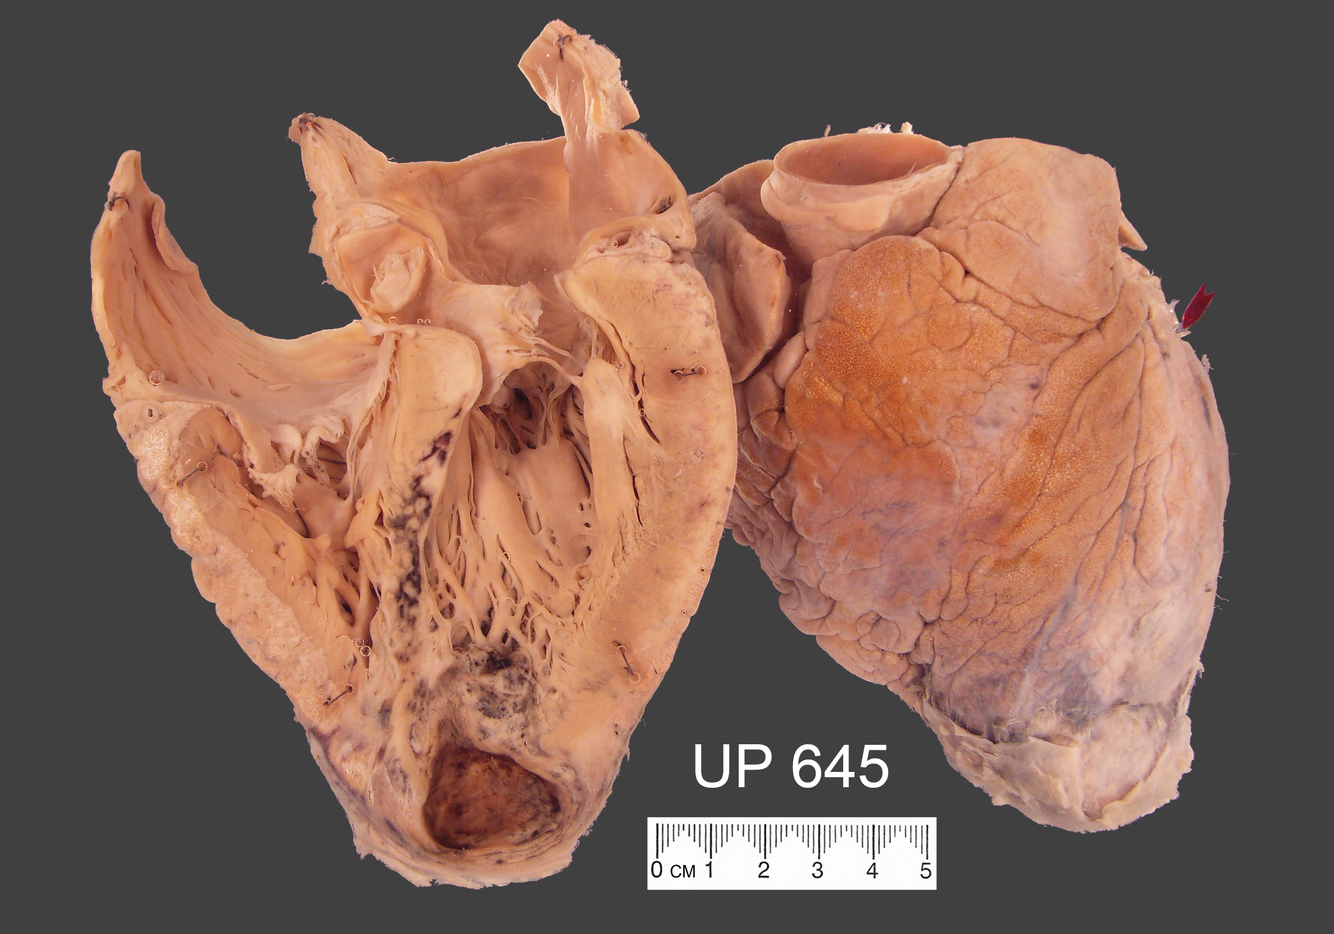

The heart shows a thinned aneurysmal dilatation of the postero-lateral aspect of the left ventricle. The myocardium of this “blown out” portion is haemorrhagic and shows a small perforation.

The circumflex branch of the left coronary artery is completely occluded by thrombus.

Ventricular rupture is a complication of myocardial infarction. It occurs in 1-2% of transmural infarcts usually in the first 4-5 days. Pericardial tamponade results if it is the free wall of the left ventricle that ruptures. If the septum ruptures then there is a left to right shunting of blood.